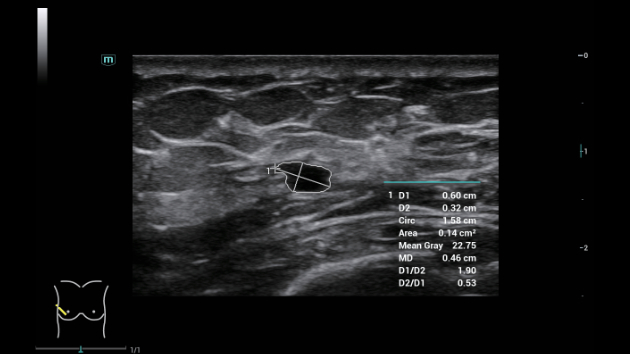

Ongeacht of u werkzaam bent in een ziekenhuis of kliniek, of uw vaardigheden aanscherpt op het gebied van algemene beeldvormingstoepassingen, vrouwengeneeskunde of cardiovasculaire specialismen, in deze serie vindt u zeer krachtige hulpmiddelen waarmee u aan kop kunt blijven.

Uitgebreide?oplossingen voor beeldvorming aangestuurd door ZST?+

Het ZST+?platform is een buitengewone innovatie en revolutie in de wereld van echografie. Het transformeert echografiegegevens van conventionele bundelvorming naar kanaalgegevensverwerking. Het overwint de traditionele afweging tussen ruimtelijke resolutie, temporele resolutie en weefseluniformiteit, en levert een uitzonderlijke beeldkwaliteit voor oneindige beeldvormingsoplossingen met non-stop verbeteringen.